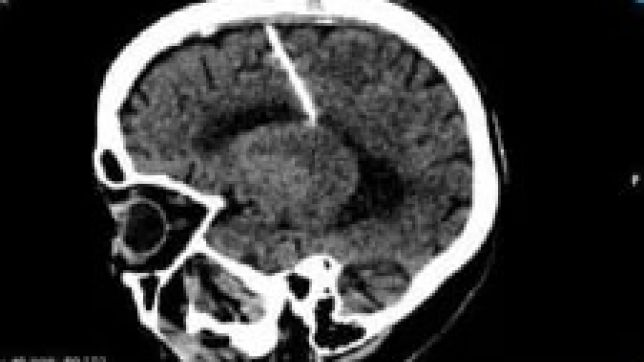

O achado inesperado ocorreu quando ela realizava um exame de tomografia. Os médicos suspeitam que ela tenha sido vítima de uma tentativa de infanticídio.

A agulha foi colocada no cérebro através da moleira. Com o desenvolvimento da criança, os ossos da região do crânio se fecharam e ela não ficou com nenhuma cicatriz. O artefato não afetou o desenvolvimento da mulher.

Os médicos decidiram que não removerão o objeto, considerando que a cirurgia poderia trazer riscos à vida da idosa.